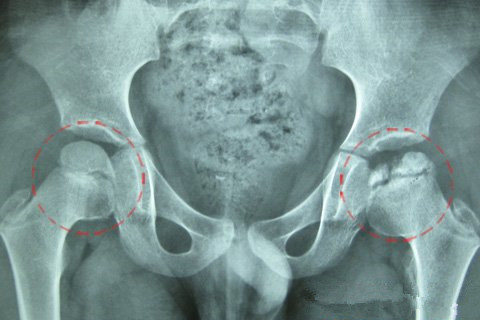

广州强直葆髋医院专家指出:作为常见的骨科顽疾,股骨头堵塞的血管是…… 【详情】

髋关节疼痛关节僵硬与活动受限病情反复,治疗效果差临床数据显示,股…… 【详情】